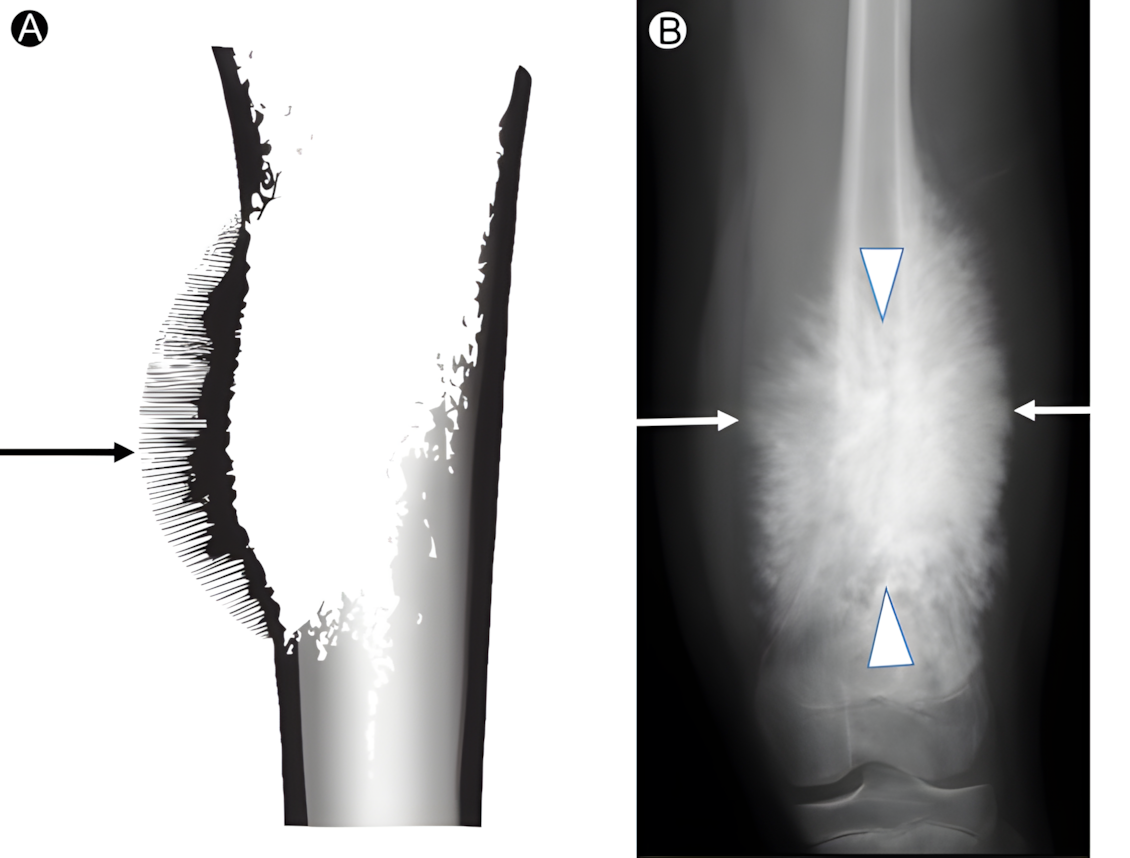

고고학 인골에서 골육종은 악성종양중 뼈에 생기는 것으로

그 특이적 소견 때문에 오진의 가능성이 별로 없는 것 중 하나다.

골육종은 소위 Sunburst Appearance라는 소견이

방사선 영상에서도 보이고

인골에서도 확인되기 때문에 진단히 확실한 악성종양이다.

지금 올라온 뉴스 하나를 보니 발뼈에 생긴 골육종이라는 것인데

형태를 보니 확실한 것 같아 그 근거를 좀 찾아 올려둔다.